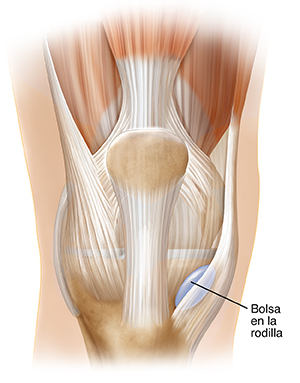

La bursa es un pequeño saco lleno de líquido. Esta sirve para amortiguar los músculos, tendones y huesos de una articulación. La inflamación de esta bolsa se llama bursitis. Los síntomas más comunes de la bursitis son: dolor, sensibilidad e hinchazón que limitan el movimiento de la articulación afectada.

La bursitis puede deberse a un evento aislado, como una caída o un golpe en una articulación. La bursitis se debe con mayor frecuencia al uso excesivo de una articulación. La repetición de los mismos movimientos irrita la bolsa y causa inflamación. Cuando ocurre esto, los otros tejidos cercanos tienen menos espacio para moverse. La bursitis es más común en las articulaciones grandes, como la rodilla, el hombro, el codo y la cadera.